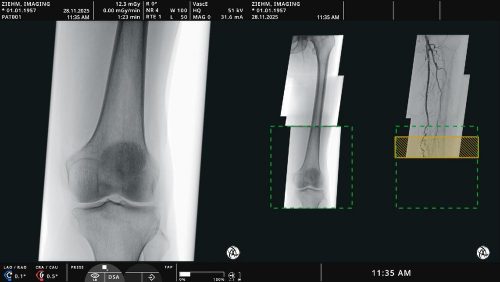

Mit der roboter- und bildgeführten Präzisionsbestrahlung lassen sich am CyberKnife Zentrum München Tumore im gesamten Körper behandeln – vom Hirn über die Wirbelsäule sowie verschiedene Körperorgane wie Lunge, Leber oder Niere bis zur Prostata. „Mit dem System betreiben wir Radiochirurgie, also eine Behandlung mit Strahlen, auf höchster Präzisionsstufe. Durch die Integration eines Bildführungssystems mit Robotertechnik erreichen wir eine Genauigkeit der Bestrahlung von unter einem Millimeter“, erläutert Prof. Dr. Alexander Muacevic, Radiochirurg und Neurochirurg am Zentrum.

Danach wird die Behandlung gestartet und läuft vollautomatisch ab. Hier setzt der KUKA Roboter im CyberKnife-System des Medizinproduktherstellers Accuray ein. „Ich vergleiche das immer mit einem Piloten im Cockpit, der ja auch sehr schnell auf Autopilot schaltet. Für uns Ärzte ist der wesentliche Job da bereits getan, wir überwachen zusammen mit den medizinisch-technischen Assistenten nur noch den Patienten. Die eigentliche Arbeit macht das CyberKnife-System autark. Und das mit einer Präzision, die kein Chirurg erreichen kann. Manuell eine Genauigkeit von 0,5 Millimeter zu erreichen, ist so gut wie unmöglich“, sagt Prof. Muacevic.

Genau diese Präzision in der Bestrahlung ist der wesentliche Vorteil des Roboters im CyberKnife-System. Mit dem System werden beispielsweise gutartige Hirntumore, sogenannte Akustikusneurinome oder Meningeome, behandelt. Diese würden ansonsten in einem bis zu sechsstündigen Eingriff operativ entfernt; anschließend wären ein gut einwöchiger Krankenhausaufenthalt und eine achtwöchige Reha notwendig. „Mit unserem virtuellen Messer können wir kleine und mittelgroße Tumore sehr gut behandeln und so eine OP ersetzen. So kann der Patient bereits am nächsten Tag wieder arbeiten gehen.“